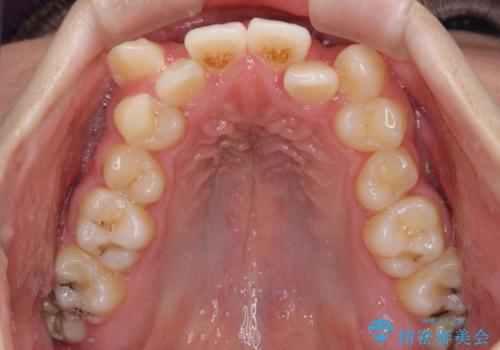

上下ともに八重歯が顕著であり、前歯のクロスバイトがあったため、上下左右の第一小臼歯4本を抜歯し、ワイヤー装置での抜歯矯正を行うこととしました。

前歯の歯列が整ったことで、歯磨きが大変やりやすくなり、患者様には大変満足していただけました。